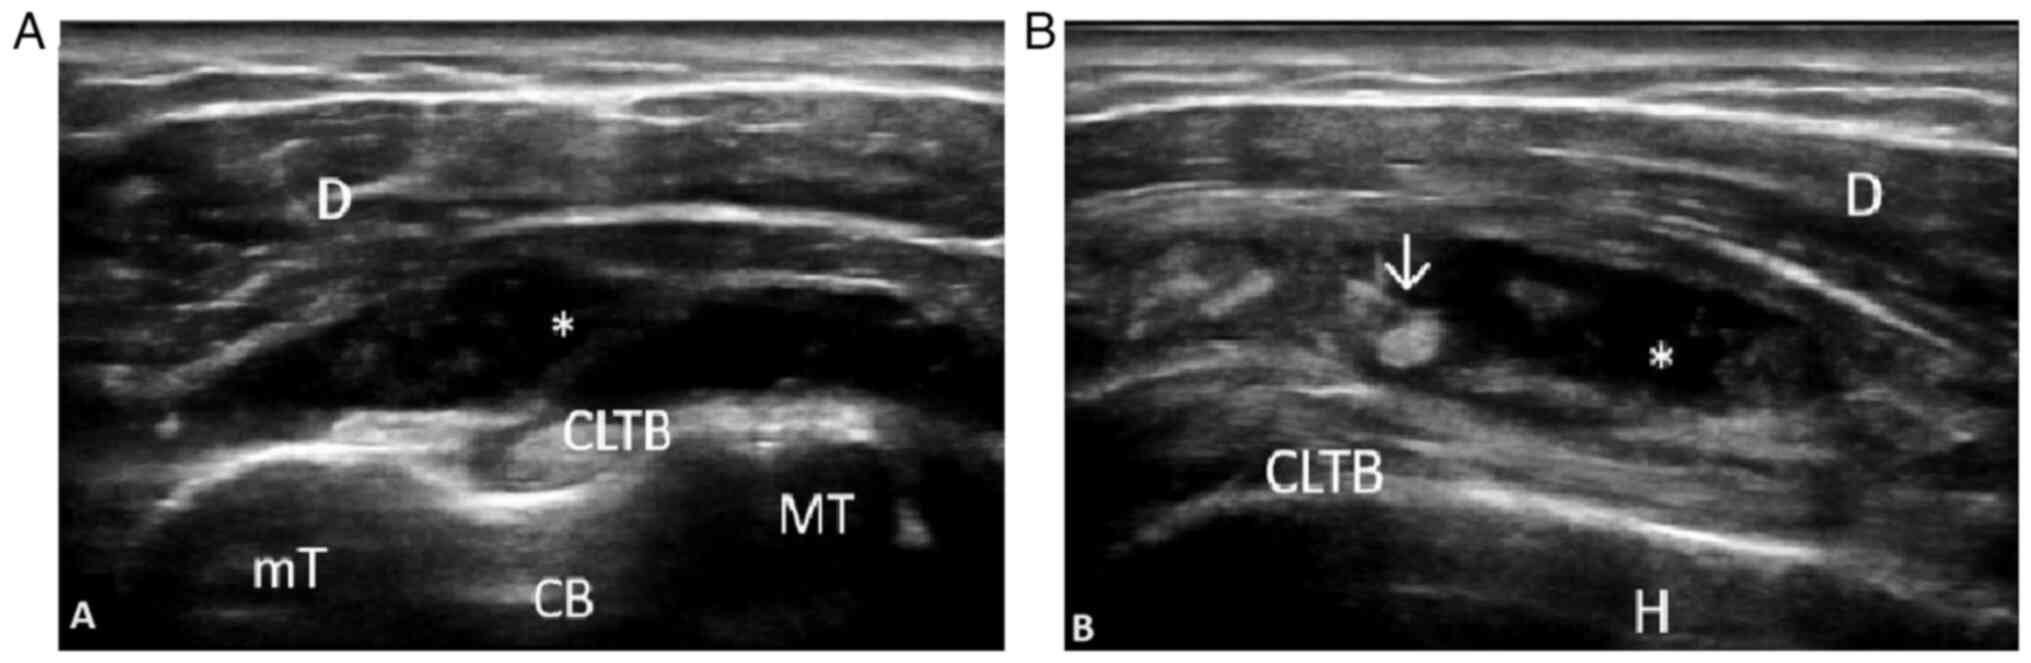

Diagnostic accuracy. As a result of several ultrasound studies performed in Europe, with regard to the detection of inflammatory lesions in PMR mostly using B-mode, and to a lesser extent, power Doppler examination, the most frequent ultrasound abnormalities described are bursitis of the subacromial/subdeltoid (SASD) bursae and tenosynovitis of the long head of the biceps tendon (LHBT), ranging from 6.2 to 100% at the shoulder level, with a higher prevalence of SASD bursitis, and less frequently, trochanteric bursitis and synovitis at the hip level (49,50). The importance of this data determined the inclusion of an ultrasound criteria for the first time in rheumatology in the 2012 EULAR/ACR Provisional Classification Criteria for PMR, increasing the specificity of the clinical diagnosis to 81% (51). Subsequently, Macchioni et al (52) revealed that the addition of ultrasound to clinical criteria increased the diagnostic performance from 81.5 to 91.3% in patients with PMR, while comparing PMR to other types of inflammatory arthritis, including RA. The diagnostic specificity in this case increased from 79.9 to 89.9% (Figs. 2 and 3). The images were obtained by examining a patient with PMR at the Emergency Clinical County Hospital of Craiova.

Transverse (A) and longitudinal (B) scan in gray scale of the long head of the biceps tendon, demonstrating anechoic moderate collection in the subacromial/subdeltoid bursa, with the presence of villonodular synovial proliferation in a 79-year old male patient (performed on a MyLabSix Ultrasound machine; Esaote SpA). mT, small tuberosity of the humerus; MT, big tuberosity of the humerus; CLTB, long head of the biceps tendon; CB, bicipital groove; *, collection; d, deltoid muscle; ↓, synovial proliferation.

Written informed consent was acquired from the patients associated with the images presented in Figs. 2 and 3.

Patient consent for publication